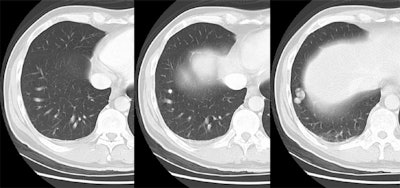

The patient shown below presented with a brain abscess. Portable plain films were of poor quality so a chest CT was done to assess for the presence of a pulmonary AVM. The lesion can be seen in the right costophrenic sulcus with a single artery and a single draining vein (simple AVM).

Cases are best viewed with a cine format which will aid in identification of the arterial and venous communications. Click here to view cine images.